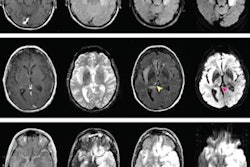

The roots of the 10-year study date back to 2002, when the researchers began to track 262 people in the Houston area who were infected with the West Nile virus. Of the 262 subjects, 117 participated in follow-up neurologic and neurocognitive evaluations, with 30 (26%) receiving MRI scans to look for cortical thinning and regional atrophy. The subjects were also given the Repeatable Battery for the Assessment of Neuropsychological Status (RBANS) to measure cognitive decline or improvement.

The MR images revealed significant cortical thinning in both the left and right hemispheres, primarily in the frontal and limbic lobes, compared with control subjects. In addition, the researchers found significant regional atrophy in the cerebellum, brain stem, thalamus, putamen, and globus pallidus.

"MRI helped us to target specific areas of the brain where we are seeing abnormal findings," Murray said. "It did not surprise us too much that we were seeing clinically that the subjects had a lot of cognitive deficits; some of them had hypoxia."